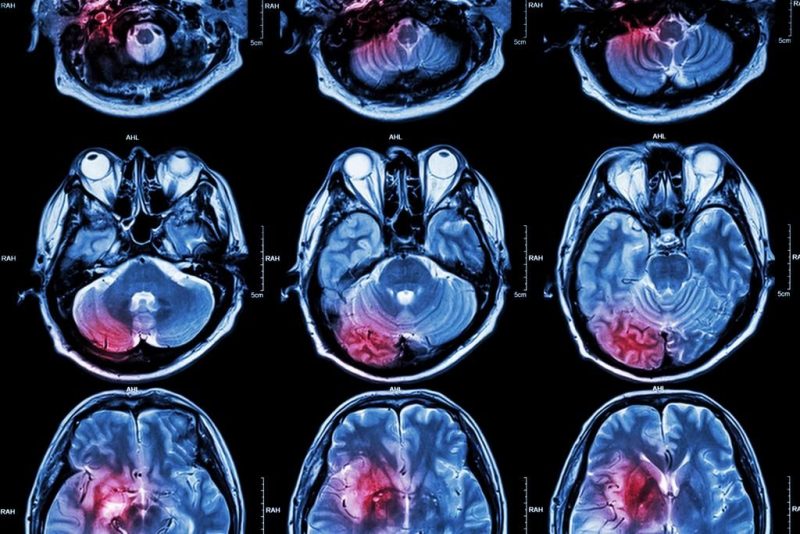

El “Estudio epidemiológico poblacional sobre accidentes cerebrovasculares”, a cargo de Sebastián Ameriso, jefe del Centro Integral de Neurología Vascular del Fleni, se inició en 2015 con el fin de “ampliar el conocimiento sobre esa patología y mejorar procesos de prevención y políticas de salud”, precisaron desde ese centro neurológico Un accidente cerebrovascular ocurre cuando se interrumpe o se reduce el suministro de sangre que va a una parte del cerebro, lo que impide que el tejido cerebral reciba oxígeno y nutrientes. En cuestión de minutos, las neuronas cerebrales empiezan a morir.

A su vez, el 88% de los ACV de General Villegas fueron isquémicos (por obstrucción de las arterias) y el resto hemorrágicos (por ruptura de vasos).